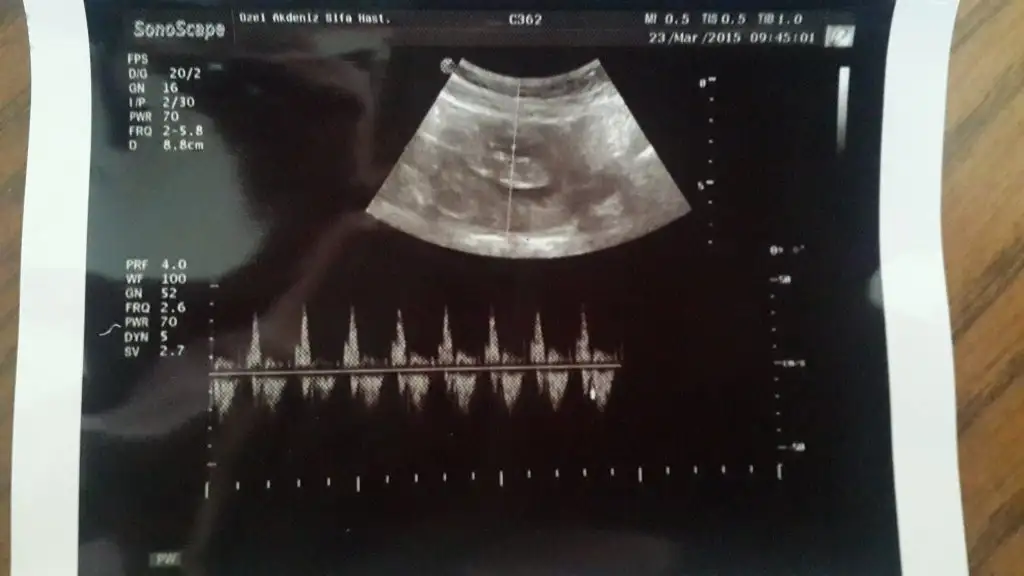

dr soylemeden siz gorun genital nub teorisi ( bebegin cinsiyeti)

Bende yorum bekliyorum ayrintilida doktor kiza benzettim dedi

mrb kizlar bende tahminlerinizi bekliyorum sat a gore 11+4 ultrasyon a gore 12 + 0